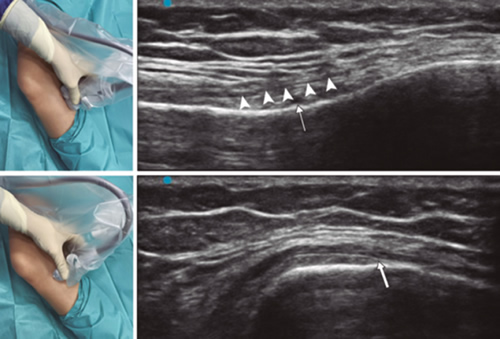

19. Lash D, Frantz E, Hurdle MF. Ultrasound-guided cooled radiofrequency ablation of the genicular nerves: a technique paper. Pain Manag. 2020;10(3):147-57.

20. Yasar E, Kesikburun S, Kılıç C, Güzelküçük Ü, Yazar F, Tan AK. Accuracy of ultrasound-guided genicular nerve block: A cadaveric study. Pain Physician. 2015;18(5):E899-904.